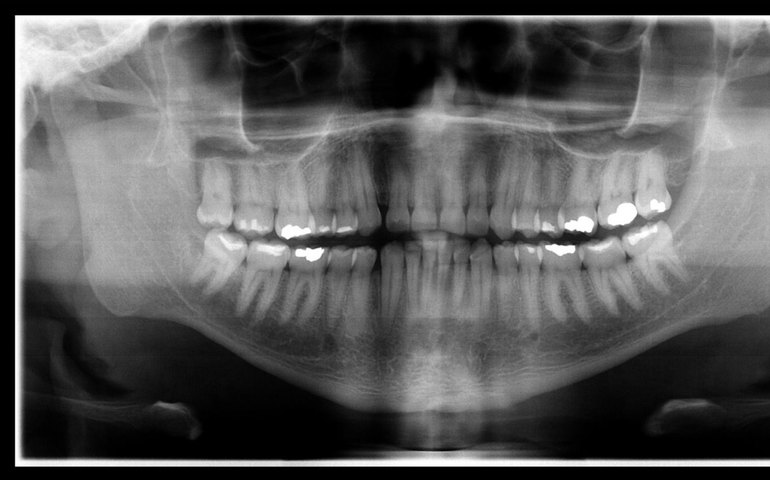

A partir de documentos solicitados pelo IML e enviados pela então suposta família da vítima, a odontolegista Isabella Lemos confrontou as imagens de antes e depois da morte, e identificou convergências quantitativas, qualitativas e morfológicas suficientes para a identificação do cadáver.

Segundo Isabella Lemos, exames odontológicos realizados durante a vida podem ser essenciais para identificação de cadáveres que chegam ao IML. Os exames disponibilizados pela família continham fotografias extra-orais, intra-orais, radiografia panorâmica e cefalometria, que, de acordo com a perita odontolegista, foram importantes para a identificação da vítima.

“Através desse caso, deu para ressaltar a importância da contribuição dos cirurgiões dentistas com as perícias de identificação odontolegal, já que, por se tratarem de metodologias comparativas, é fundamental que os dentistas que atuam no atendimento preencham adequadamente o prontuário odontológico e que guardem também toda a documentação, como por exemplo os exames radiológicos, modelos em gesso, fotografias do paciente”, aponta Isabella.